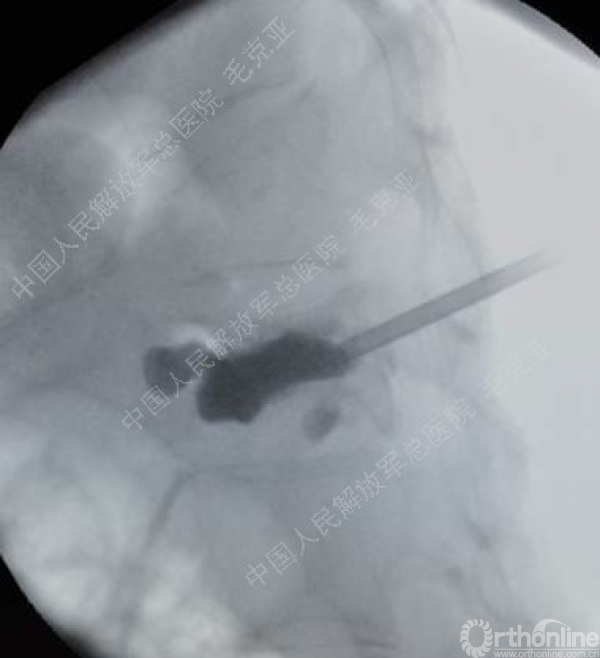

导语:随着社会老龄化的不断加速,骨质疏松性椎体压缩骨折作为一种普遍存在的老年骨科疾病已经成为现今骨科界的一个热点话题。传统的保守疗法治疗效果不佳,而现有的椎体增强技术又具有多种风险和缺陷。针对这种现状,中国人民解放军总医院毛克亚教授提供了一种新的解决方法。